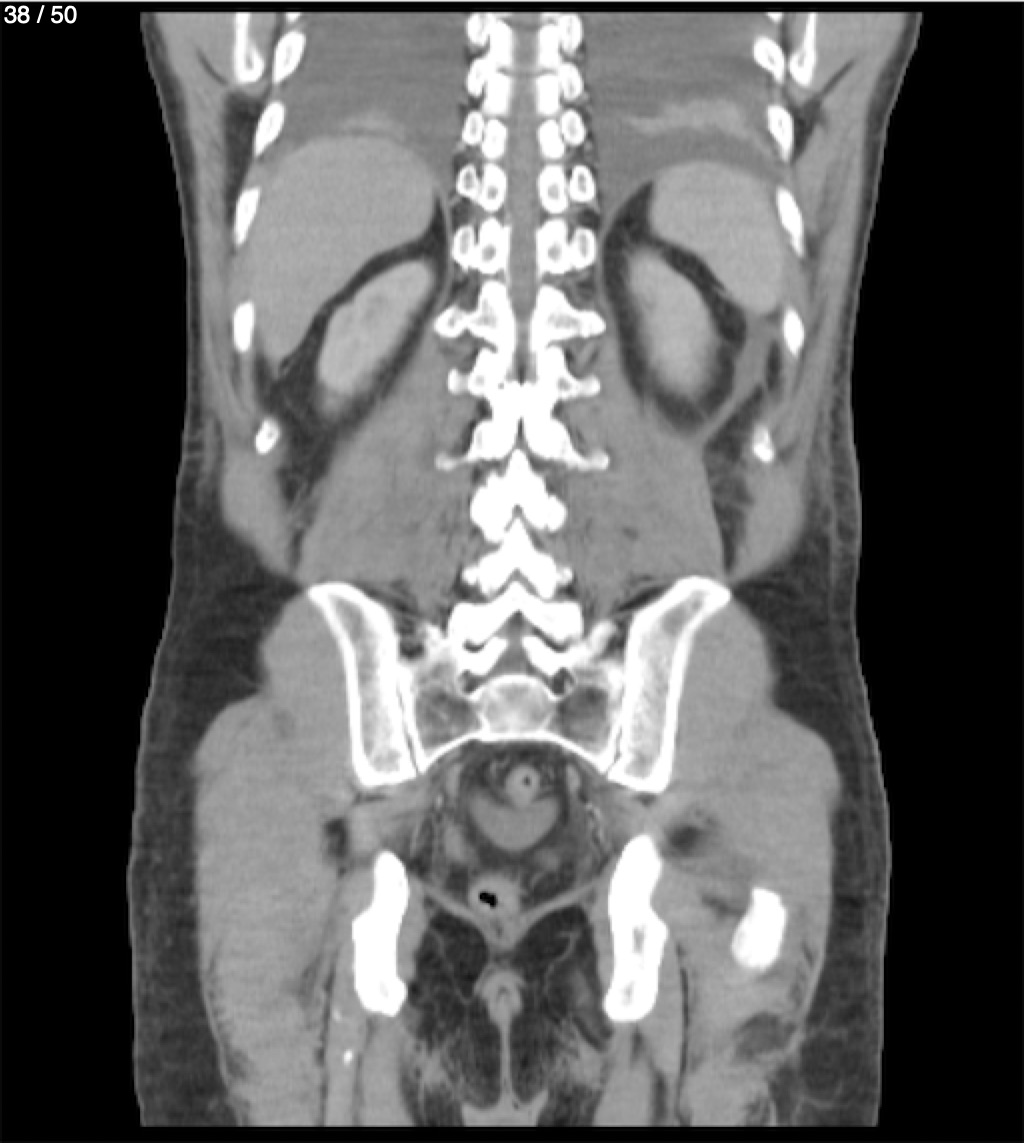

Alonso Victorio Ruiz 62A - T.C Abdomen Syc